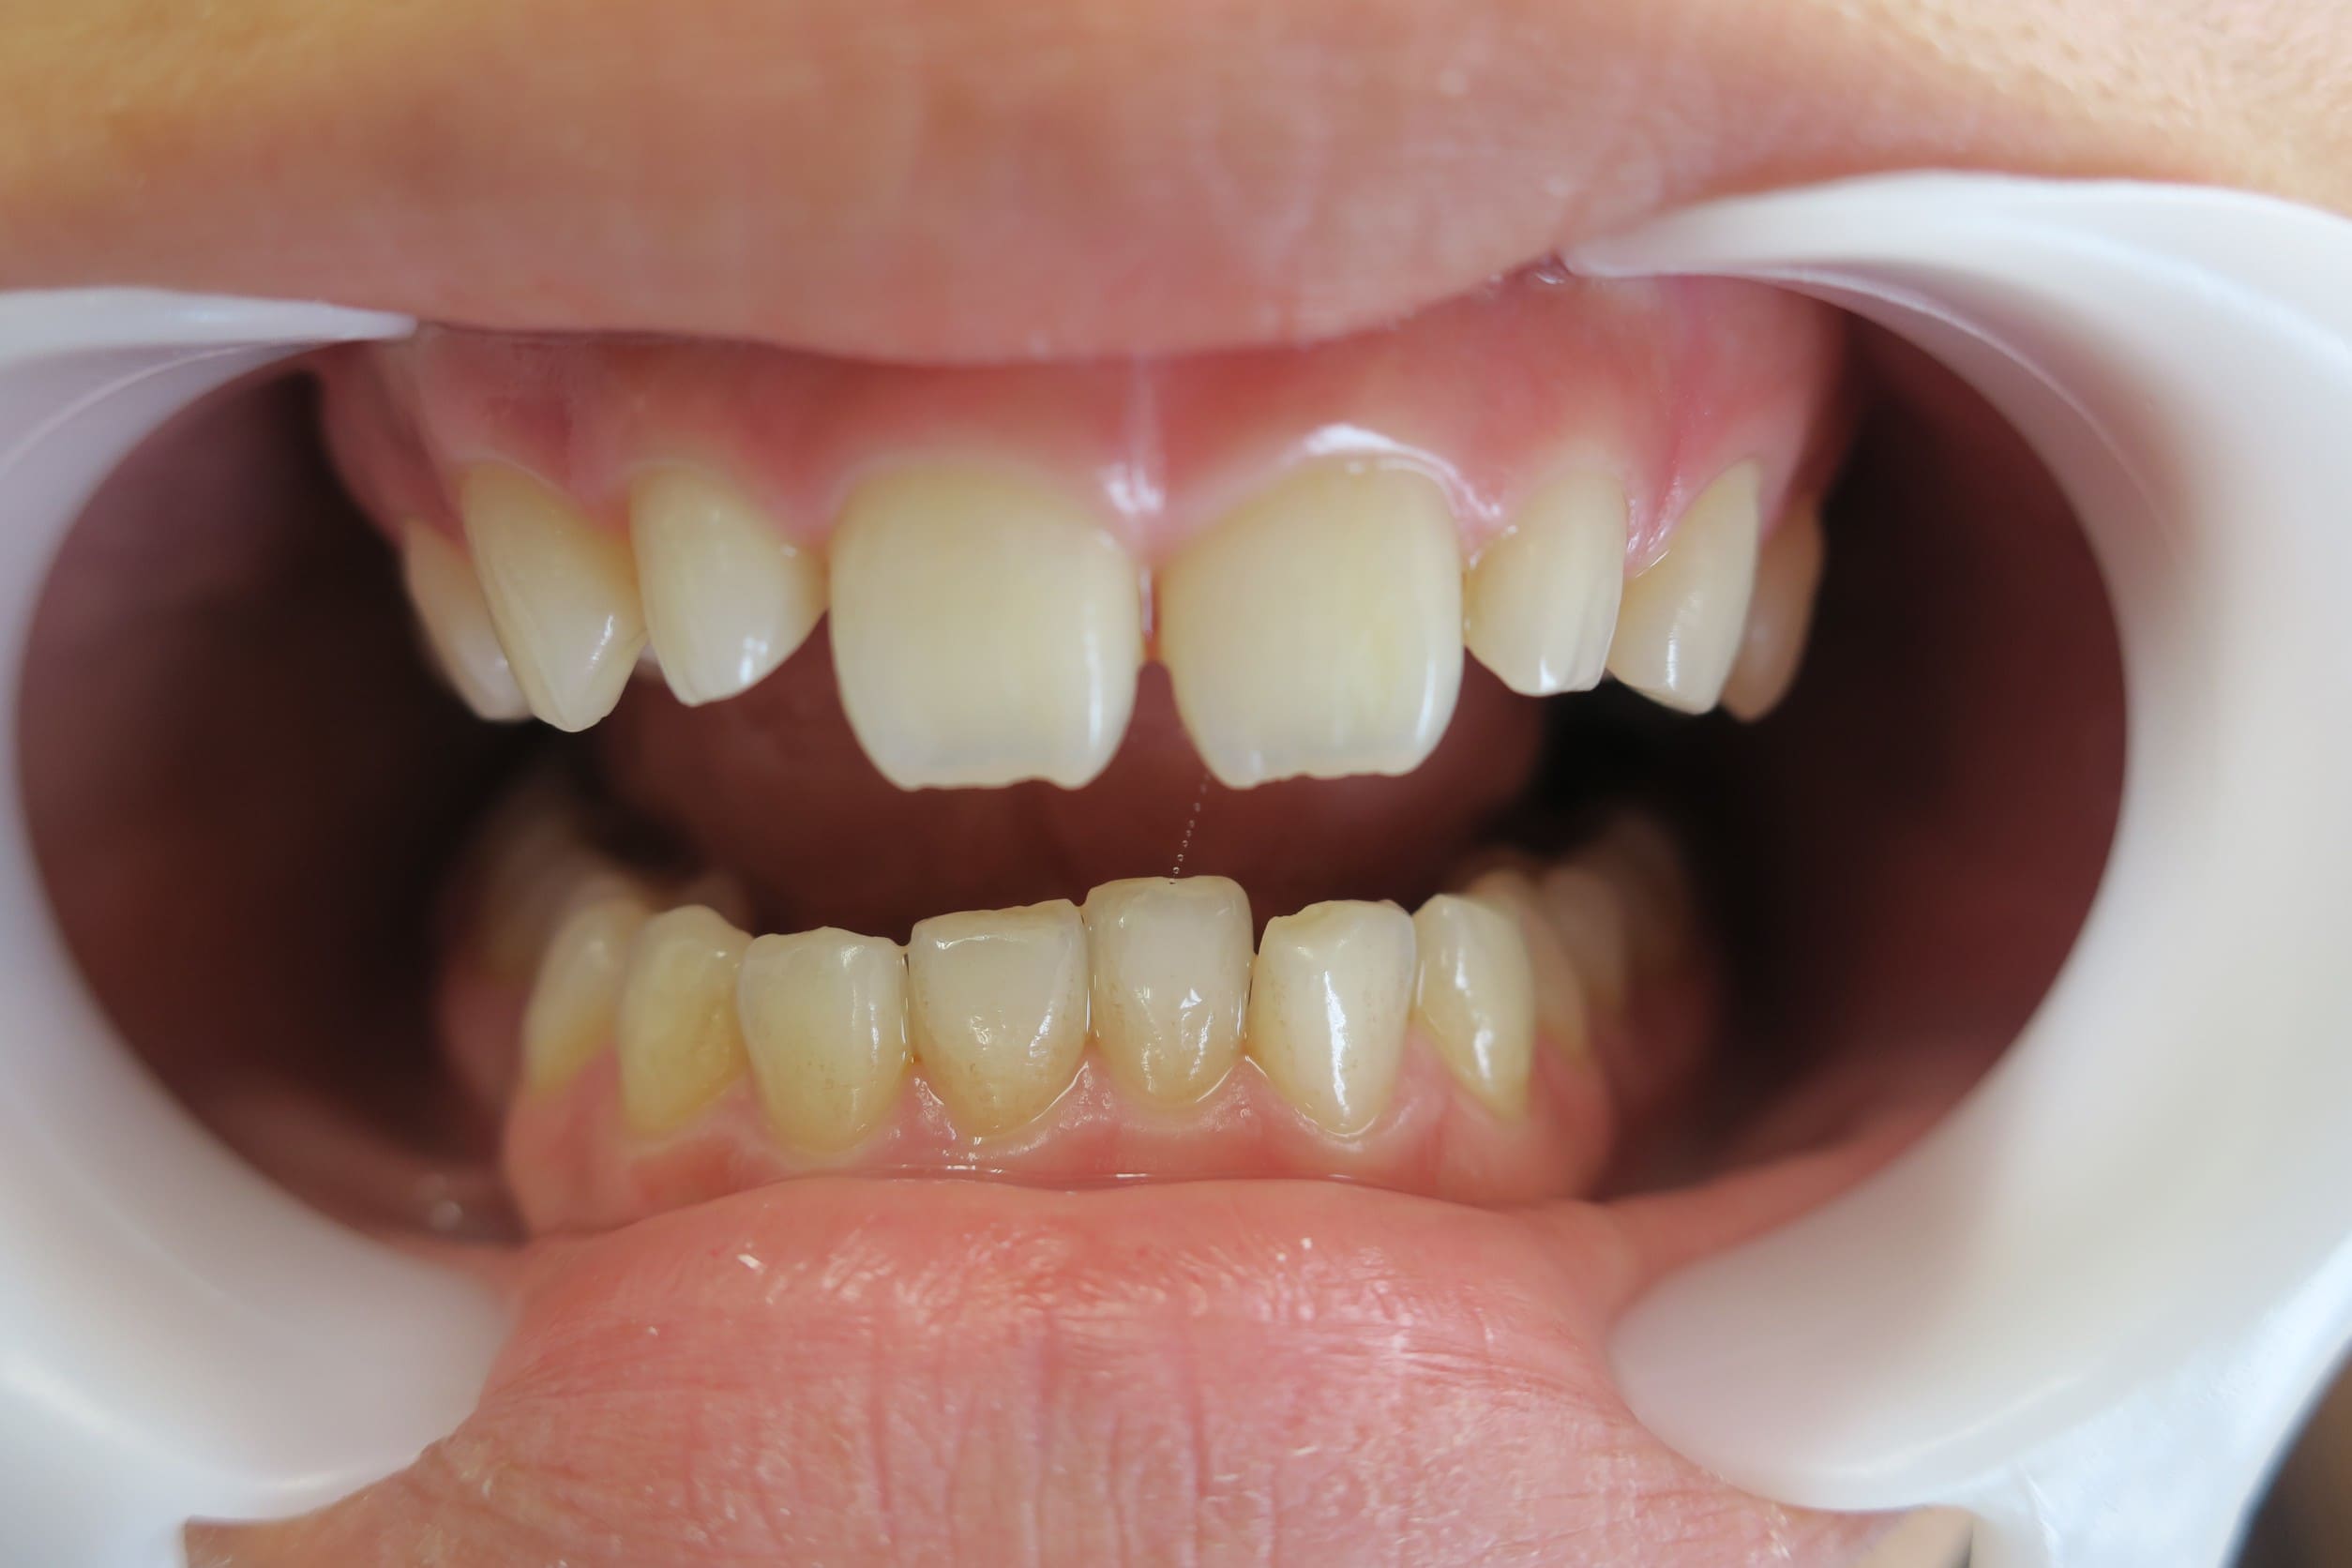

● C4を超え歯根までの虫歯を抜歯、スペースを利用して歯並び全体を整えた症例

藤沢デンタルオフィスの虫歯や破折で抜歯後の部分矯正